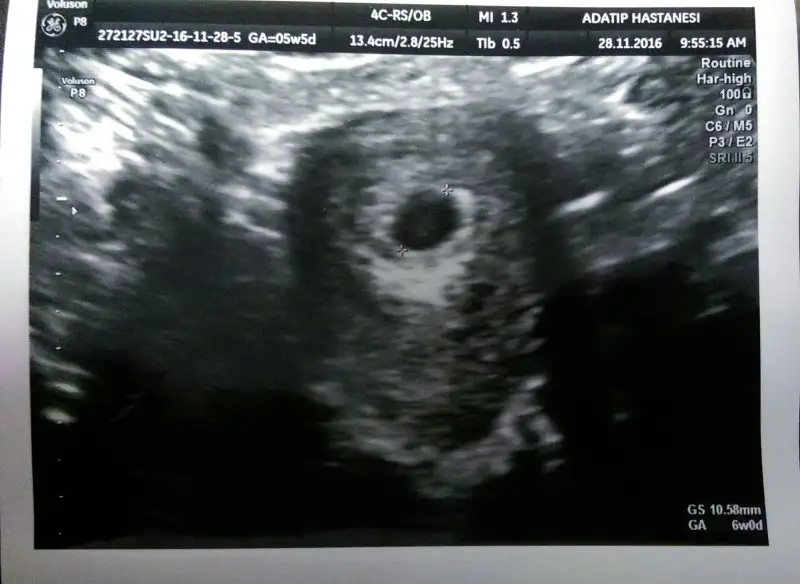

amin inşallah canım ultrason çıktısında 6w0d yazıyo ama acaba son adet tarihime göre mi yazdı öyle acaba diyorum

Melissa81 canım bak ultrasonda üstte GA 5w5d diye yazıyor ama sağ altta da GS 10.58 mm GA 6w0d diyor yani son adete göre 5+5 ama keseye göre 6+0 mı demek istemiş oluyor

Elmol şimdi anladım 5 week 5 day yani 5 hafta 5 gün sat a göre 6week 0 day 6 hafta 0 gün.bu da kesenin boyutuna göre maşallah Gelişimi gayet güzel